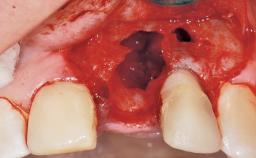

This 43-year-old male patient, a non-smoker, came to our practice because of a fracture of tooth 12 caused by a bicycle accident. Due to the combined para- and infrabony crown and root fracture, tooth extraction, and subsequent implant placement were suggested to the patient as the therapy of choice. The patient had high esthetic expectations with regard to the treatment outcome and asked for an immediate fixed provisional restoration. His individual esthetic risk profile summed up to a medium esthetic risk.

Placement Protocol Immediate implant placement

Tooth Site Maxillary incisor or canine

Socket Integrity Sufficient, with intact bone walls

Bone Volume Sufficient, with intact walls